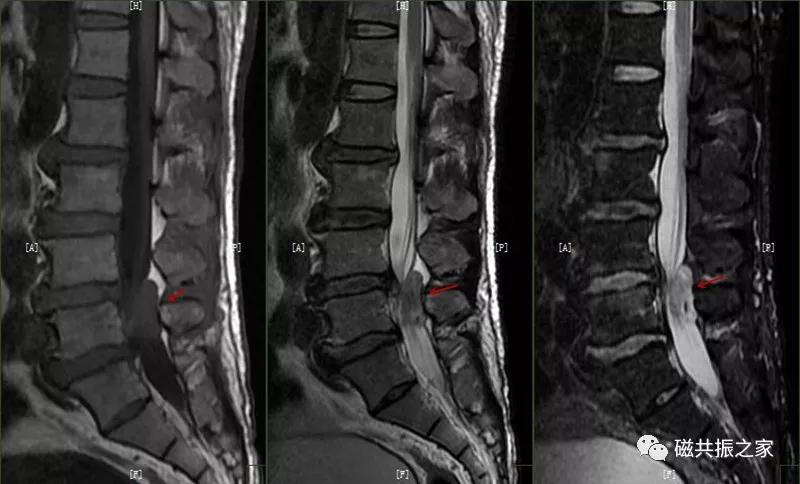

椎体边缘骨,类似于Schmorl改变,一类是椎体生长板和椎体二次骨化中心软骨发育异常,致其不能完全愈合,造成的椎间盘疝入其间,形成边缘体的椎体边缘骨。

椎体生长板和椎体二次骨化中心软骨发育异常,致其不能完全愈合,造成的椎间盘疝入其间,形成边缘体的椎体边缘骨。

另一类是椎体后缘骨内软骨结节,椎间盘疝入骨内,形成椎体后缘的Schmorl结节样改变,椎体终板及髓核等突入其中,椎体骨质增生,常见于L4、L5椎体下缘。

椎体后缘骨内软骨结节,椎间盘疝入骨内,形成椎体后缘的Schmorl结节样改变,椎体终板及髓核等突入其中,椎体骨质增生,常见于L4、L5椎体下缘。